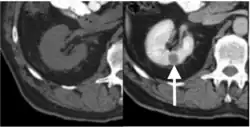

Unenhanced (left) and nephrographic phase (right) CT scans display a 1-cm low-attenuation PRCC tumor (arrow) in the right renal cortex[8]

Contrast-enhanced computed tomography (CT) is most commonly used to identify the subtypes of RCC. PRCC can be differentiated from other types of RCC due to its distinguishing features, displaying a small hypovascular renal tumor on T2 weighted images.[7] Typically, PRCC tends to appear homogeneous while clear cell RCC is likely to be in a heterogeneous form when the tumor is less than 3 cm in diameter.[30] Comparatively, in cases of tumors larger than 3 cm in diameter, PRCC is generally heterogeneous with areas of necrosis and hemorrhage compared to chromophobe RCC.[8][31] Solid, small PRCC tumors (<3 cm in diameter) are more easily viewed on nephrographic, excretory phase images rather than on unenhanced, corticomedullary phase images.[8]